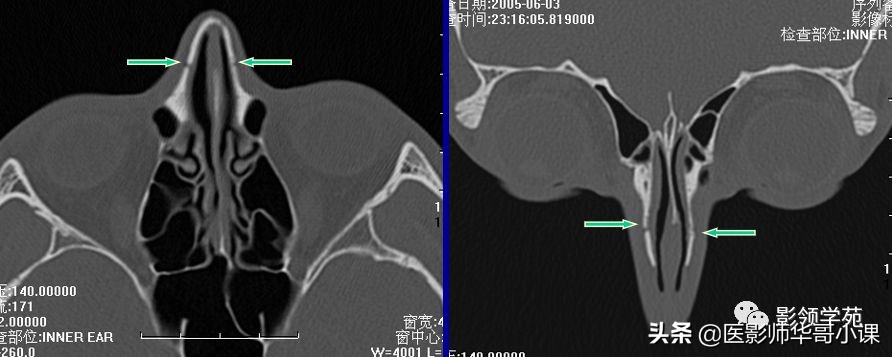

双侧鼻骨骨折

双侧上颌骨额突骨折

鼻中隔骨折